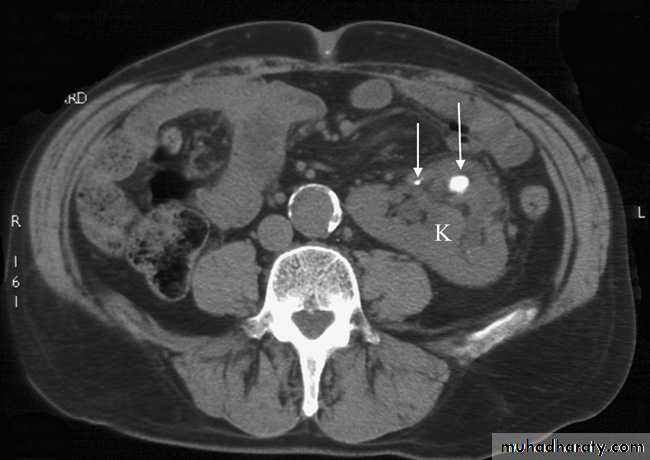

Computed tomography without intravenous contrast medium is exquisitely sensitive for the detection of calculi.

It is used in place of IVU for the detection and precise anatomical localization of stones prior to treatment in most centres

Computed tomography is now widely used to evaluate urinary tract obstruction .In acute obstruction, non-contrast enhanced CT sensitively demonstrates calculi and the unopacified, dilated collecting system can frequently be traced down to the point of obstruction .

Non-contrast CT is often used in acute ureteric colic, as an alternative to IVU, in patients with an allergy to intravenous contrast medium.